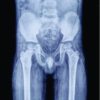

Case Report: Authors report a case of isolated carpometacarpal dislocation of the right thumb, in an adult, successfully managed conservatively. At 15 months follow up the patient had full function of the hand without any clinical or radiological evidence of instability or posttraumatic arthritis.